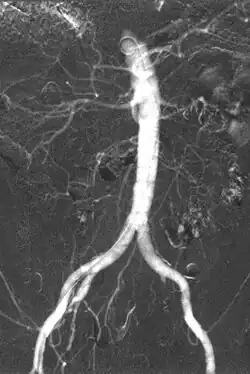

- Angiography (arterial investigations)

Iodinated contrast contains iodine. It is the main type of radiocontrast used for intravenous administration. Iodine has a particular advantage as a contrast agent for radiography because its innermost electron ("k-shell") binding energy is 33.2 keV, similar to the average energy of x-rays used in diagnostic radiography. When the incident x-ray energy is closer to the k-edge of the atom it encounters, photoelectric absorption is more likely to occur. Its uses include:

Carbon dioxide also has a role in angioplasty. It is low-risk as it is a natural product with no risk of allergic potential. However, it can be used only below the diaphragm as there is a risk of embolism in neurovascular procedures. It must be used carefully to avoid contamination with room air when injected. It is a negative contrast agent in that it displaces blood when injected intravascularly.